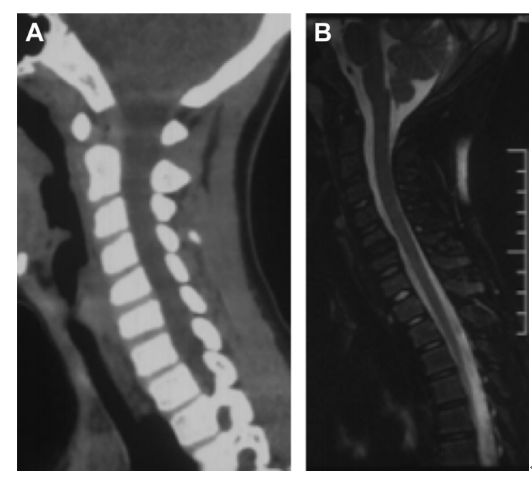

齿状突加冠综合征(Crowned dens syndrome)是指患者以急性颈痛伴随颈椎活动受限就诊,常伴发热,且影像学上表现为齿状突上方或周围出现大小不一、高密度、不规则的钙沉积影,但主要发生在齿状突后侧。因影像学征象犹如齿突戴上了一顶皇冠(如下图),因而得名齿状突加冠综合征,是因钙盐晶体在枢椎齿突周围软组织中沉积形成的。早在1985年,Bouvet等 (Arthritis Rheum, 1985) 首先报道此病。

颈椎CT冠状位重建显示犹如齿突戴上了一顶皇冠故得名齿状突加冠综合征